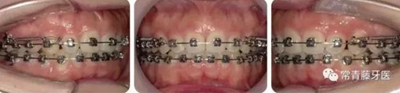

治療過程

治療8個月,換0.018*0.025"CuNiTi弓絲,植入支抗釘,植入位點為上頜第一磨牙根上方顴牙槽嵴處,使其與牙根平行。同時嘗試性牽引遠移上牙列。

治療12個月,更換為0.018*0.025”不銹鋼方絲,鎳鈦螺旋彈簧牽引內(nèi)收上牙列,同時下頜配合Ⅱ類牽引。